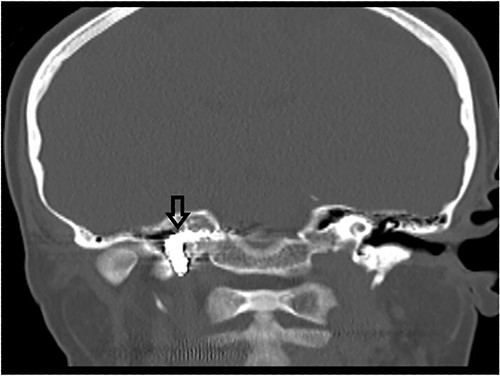

The patient underwent functional endoscopic sinus surgery. Her surgery was uneventful, and all sinuses were opened and cleaned from polyps and fungal debris. During surgery, a non-pulsating bulging at the lower lateral region of the right sphenoid sinus was noticed. This swelling was thought to be a bulging of a dehiscent ICA which may be a normal variant in some patients. Therefore, this bulging mass was not touched and was totally avoided during the procedure. The postoperative recovery period was uneventful and she was discharged the following day. However, on the 13th postoperative day, she presented to the emergency department with severe epistaxis, unconscious and blood pressure was unrecordable. After resuscitation with intravenous fluids and massive blood transfusion with 17 units of packed RBCs, the patient relatively improved and regained consciousness. Anterior and posterior nasal packs were inserted. The CT angiography showed pseudoaneurysm in the petrous segment of the right ICA (Fig. 2). The interventional radiologist performed occlusion with ballooning of right ICA for 45 min without developing motor or cognitive dysfunction, indicating a good compensation by the left ICA. Total occlusion, using multiple coils, was deployed proximal and distal to the aneurysm. Patient was discharged 2 days later. During the follow-up of more than 10 years no neurological deficit was noticed. Recent CT scan showed stable sinus disease and total occlusion of the right ICA (Fig. 3).

CT scan, showing complete occlusion of the right ICA at the petrous and cervical parts (arrow).